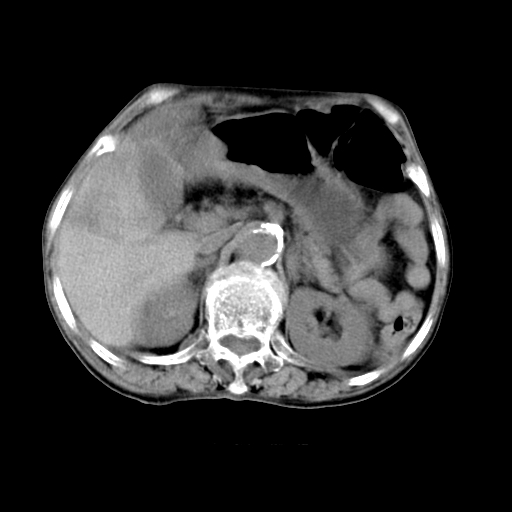

标题: CT19149:女,68岁,腹胀、恶心两周。 [打印本页]

女,68岁,腹胀、恶心两周,先做ct平扫,当时家属不同意强化,6天后家属要求增强扫描。

1、胃窦癌; 2、局灶性脂肪肝。

1)胃窦壁厚,考虑胃窦癌?建议行胃镜检查。 2)局灶性脂肪肝。